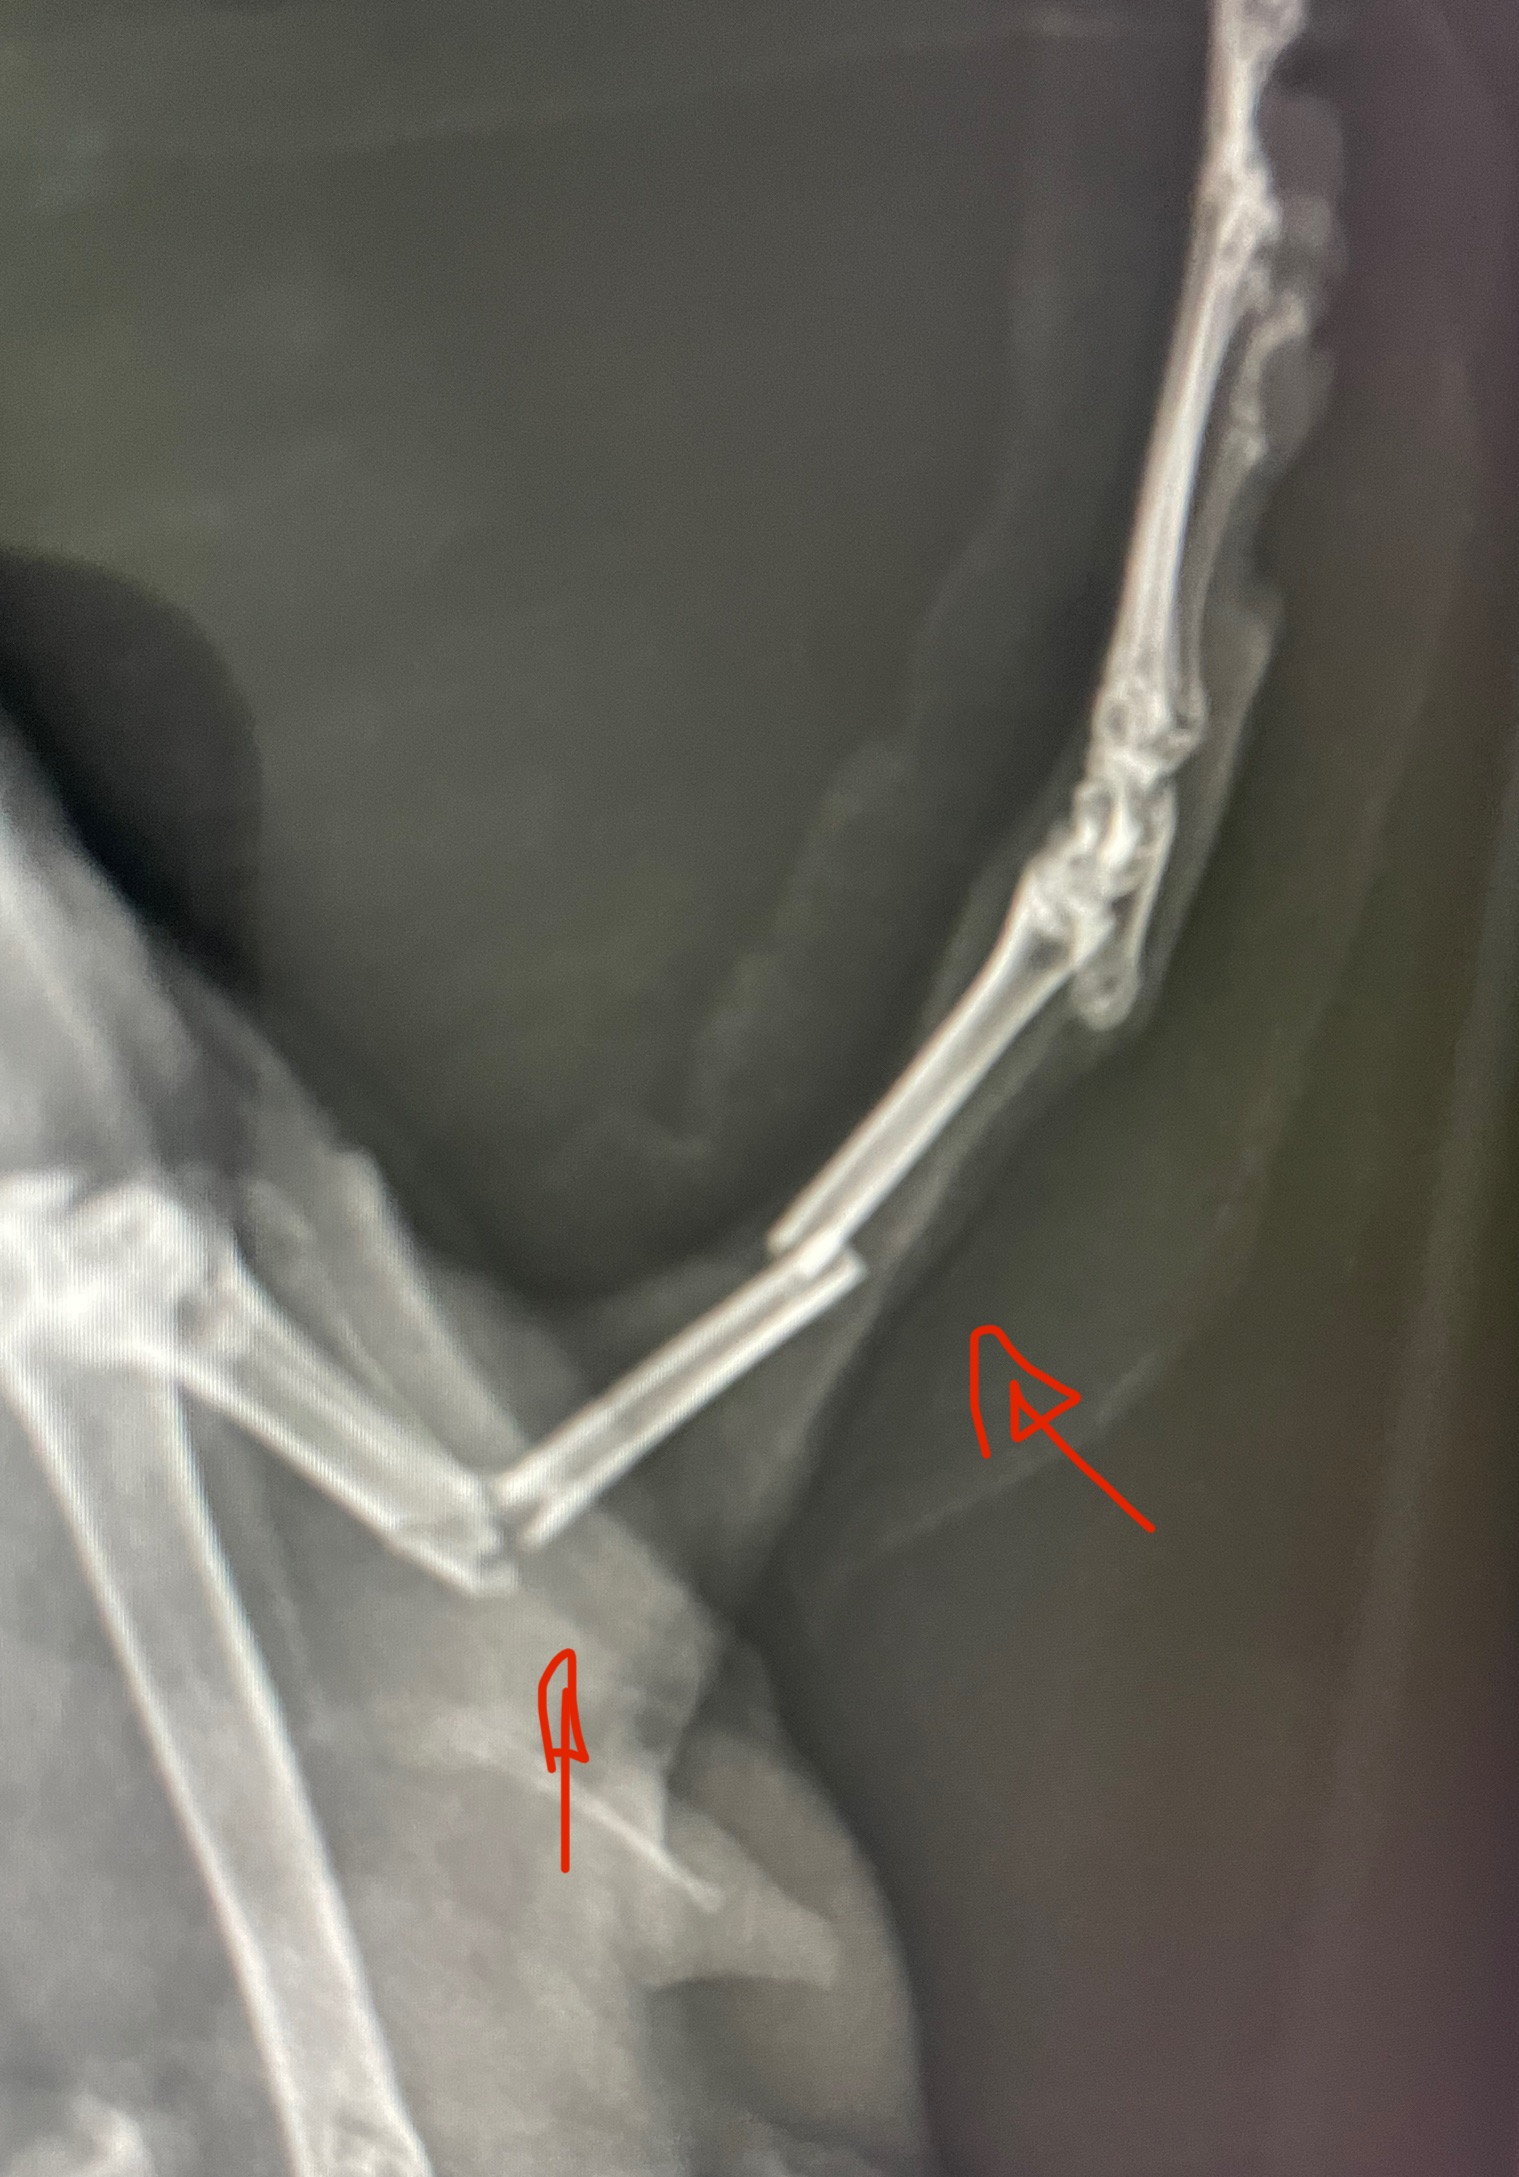

チンチラ・ウサギの四肢骨折(エキゾチックアニマル)さいたま市/南浦和/川口市/動物病院